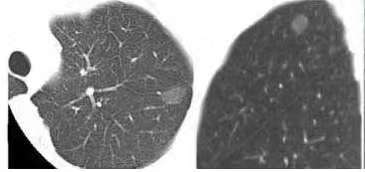

原位癌和微浸润腺癌在影像上(胸部CT)是不可能100%确诊的,除非切下来经过病理诊断才能确定,说白了影像上只能是猜测,只不过经验丰富的胸外科医生和影像科医生猜测的更准而已,还有一个真相是病理上有时候也很难区分,对于同一份肿瘤组织,不同的病理科医生诊断不一致,诊断为原位癌的,其他病理科医生也许诊断为微浸润腺癌,反之亦同。因为病理医生判断存在主观性,加上病理学诊断依据都有局限性。但是影像学正好可以弥补这些差异,因为原位和微浸润的影像学表现都是以磨玻璃为主的,微浸润可能会有实性成分,实性成分不会超过50%。都是接近百分百治愈,这两者区分其实意义不大,微浸润也可能停留很长时间不变。那么我们就无需纠结到底是原位癌还是微浸润腺癌。